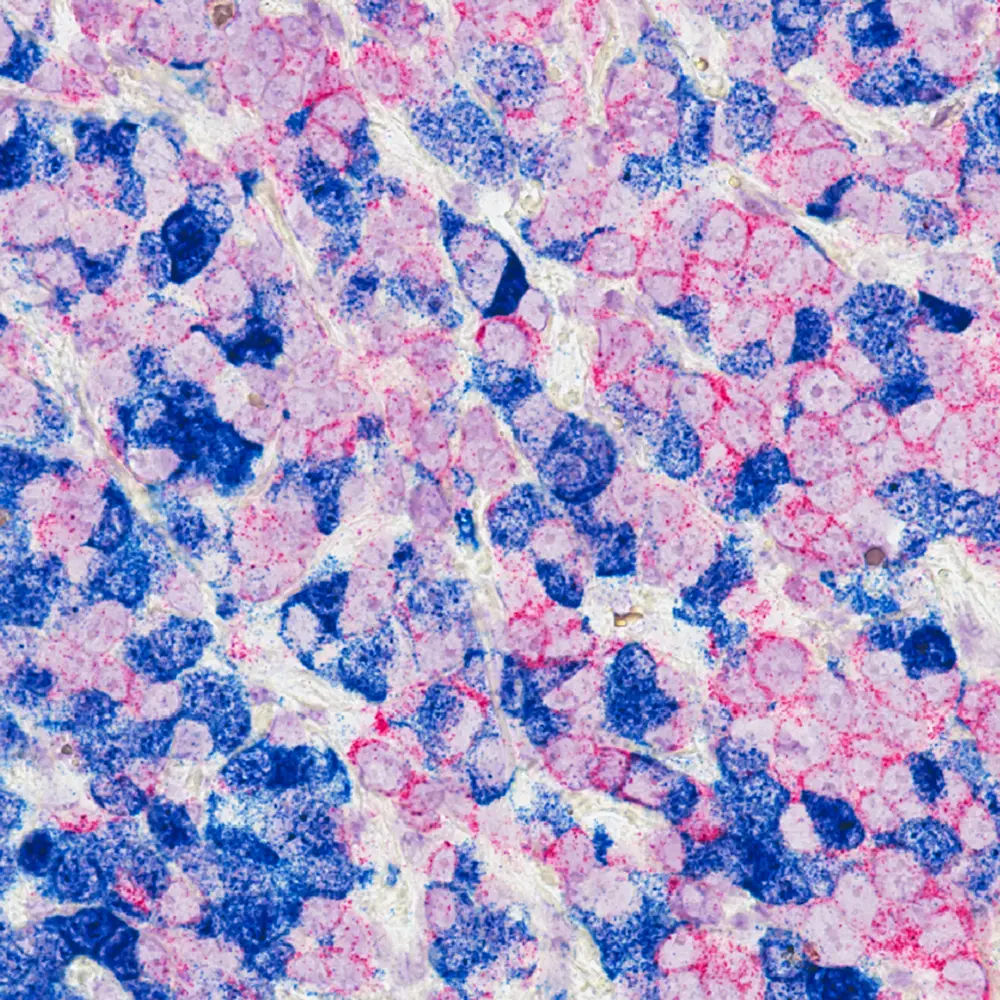

Borstkankercellen

Cellules de cancer du sein (c) National Cancer Institute